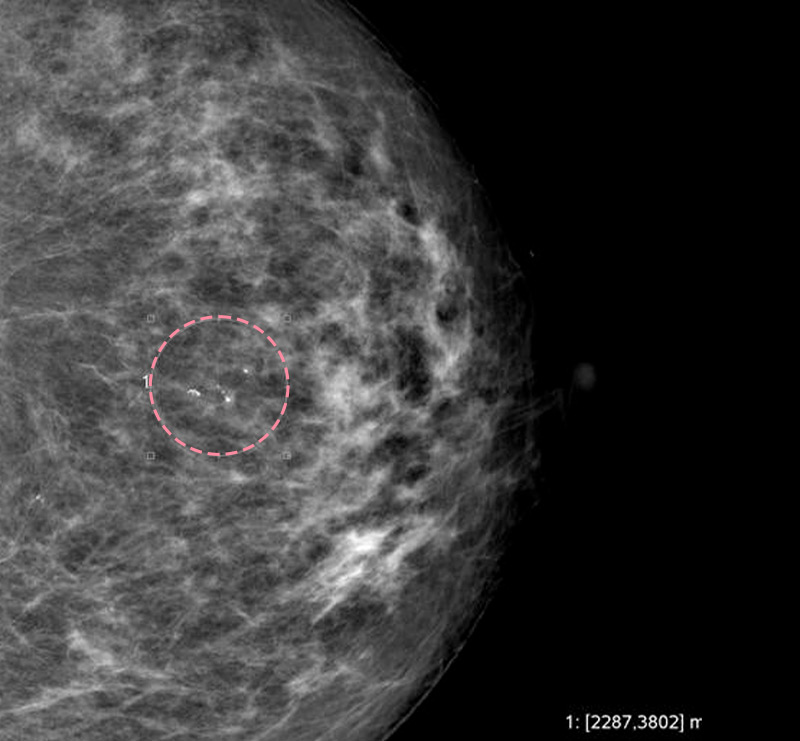

맘모톰시술 후 병리조직검사에서 상피내암(조기유방암)으로 진단되어 대학병원으로 연계해 드린 환자분의 사례입니다. 암을 초기 단계에 찾음으로써 항암치료 없이 간단한 수술을 통해 치료가 가능하였습니다.